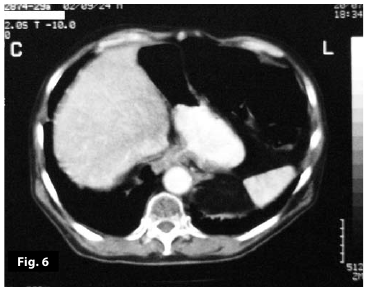

Figure5

Figure6

Figure5-6